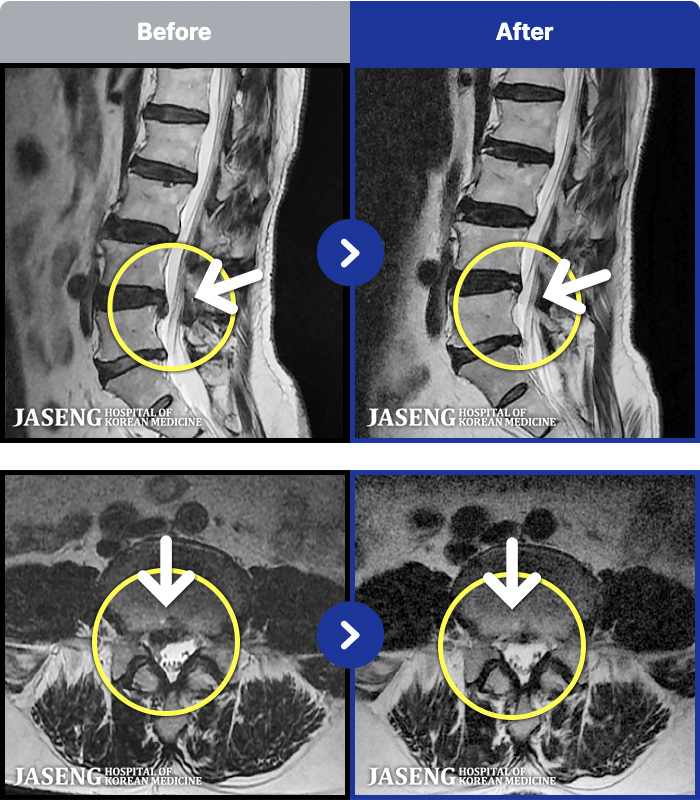

1,240 MRI ũ ʸ Ȯϼ.

MRI ġ

Ƹ ϰ ־.